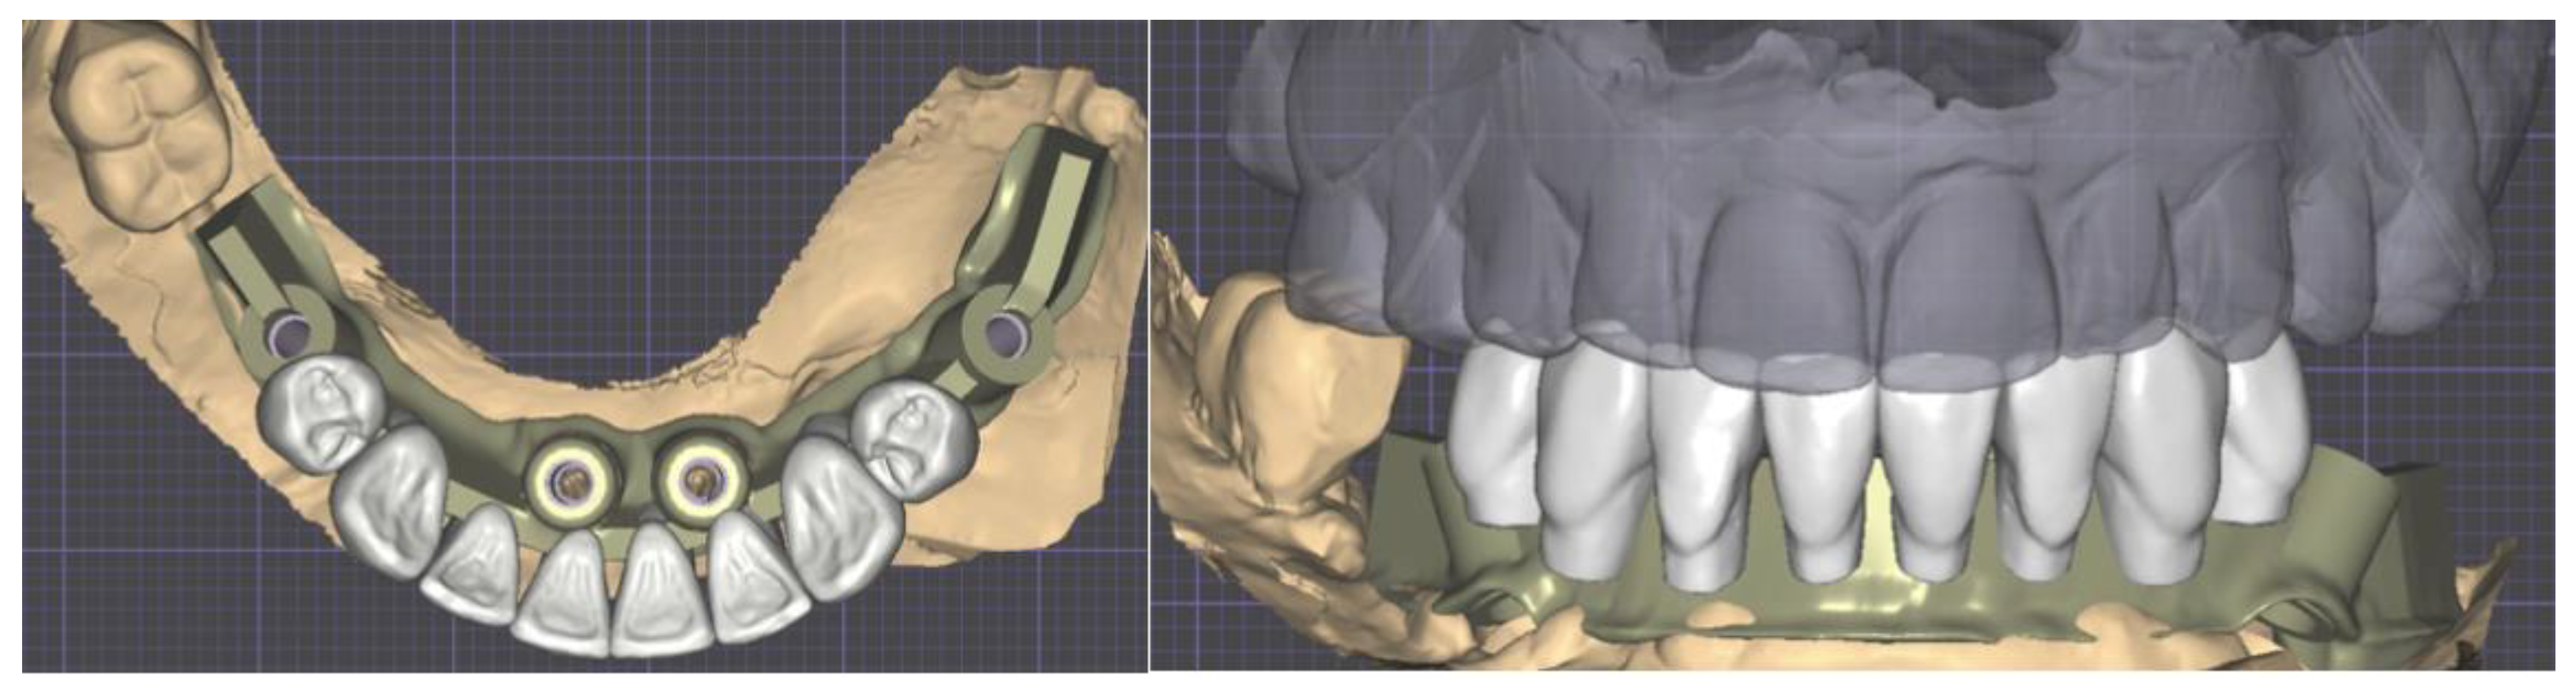

2.2. Provisional Prosthesis